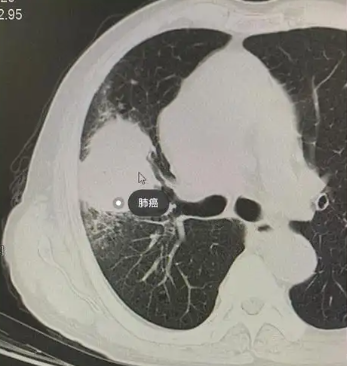

据悉,肺癌又称原发性支气管肺癌,是起源于支气管黏膜或腺体的肺部原发性恶性肿瘤,可分为小细胞癌和非小细胞癌两大类,55~65岁人群高发,男性多于女性,男女比约为2.1:1。其临床症状多隐匿,早期常表现为无痰或少痰的刺激性干咳,随着病情发展,会出现咳痰、咯血、胸痛、胸闷、气急等症状,晚期还可能出现消瘦、恶病质,甚至因继发感染导致肺炎、胸腔积液等并发症,引发呼吸衰竭而危及生命。近年来,随着体检意识的提升和影像技术的发展,肺小结节检出率逐年上升,40岁以上成年人检出率达20%左右,60岁以上人群更是高达40%,其中2%-5%可能为恶性,如何精准诊断、科学治疗成为临床诊疗的重点与难点。

邹英华主任介绍,肺癌介入治疗主要分为经血管性和非血管性两大类,核心优势在于精准、微创、高效、低毒,相较于传统外科手术“开大刀”的创伤和全身放化疗的副作用,介入治疗仅需通过2毫米的微小创口,在CT、DSA等精准可视影像设备引导下,将导管、导丝等器械送入病变部位,通过局部灌注化疗药物、阻断肿瘤供血动脉、消融肿瘤细胞等方式,精准打击肿瘤,既能最大程度杀伤肿瘤细胞,又能减少对周围正常肺组织和全身器官的损伤,有效降低术后并发症发生率。对于无法耐受外科手术的老年、合并多种基础疾病的患者,以及中晚期肺癌患者,介入治疗可有效控制肿瘤进展、缓解症状;对于早期肺小结节,介入消融治疗可实现媲美外科手术的根治效果,且能最大程度保留肺功能。

67岁的陈大爷(化名),便是邹英华主任用冷冻消融技术成功救治的一位早期肺癌患者。陈大爷常年吸烟,每年都会定期体检,2023年上半年,体检胸部CT检查显示,其右肺上叶有一个直径约1.8cm的磨玻璃结节,进一步穿刺活检后,被确诊为早期肺腺癌。由于陈大爷年事已高,合并有高血压、冠心病等基础疾病,身体无法耐受外科手术切除,当地医院建议采取全身放化疗治疗,但陈大爷及其家人担心放化疗的副作用,迟迟不愿接受治疗,四处打听更安全、微创的治疗方式。

经亲友推荐,陈大爷在家人的陪伴下,前往北大第一医院就诊于邹英华主任的门诊。邹英华主任接诊后,耐心细致地询问了陈大爷的病史、吸烟史和既往治疗情况,仔细查看了他带来的所有检查报告,随后安排他进行了增强CT、肺功能、凝血功能等全面的术前检查,进一步明确结节的位置、大小、形态及血供情况,同时评估他的身体耐受度。经过详细评估和多学科会诊讨论,邹英华主任认为,陈大爷的肺癌处于早期,结节位置较表浅,且身体基础状况虽有不足,但具备介入冷冻消融治疗的指征,冷冻消融术创伤小、恢复快、副作用小,可精准清除肿瘤细胞,同时最大程度保留肺功能,非常适合陈大爷的病情。